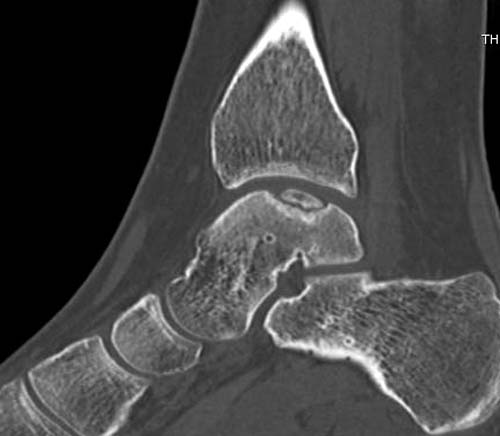

Разбираемый случай не имеет ничего общего с классическим Аваскулярным Некрозом Таранной кости. Здесь так назывемый (osteochondral defect) или osteochondritis dissecans (OCD) таранной кости, при котором патология локализуется в медиально-верхнем нагрузочном отделе. В основном OCD

встречается после хронической травмы, но бывают случаи врожденного генеза, которые обнаруживаются при случайных исследованиях.

Симптоматология  OCD выражается слабым отеком, а более сильные боли наступают после физической нагрузки. В отличие от АВН тарана, когда боли постоянные, а при OCD боли изчезают после отдыха. В начальных стадиях

на рентгенограммах не всегда заметны склерозные участки, и поэтому в большинстве диагноз устанавливается поздно. Приход КТ и МРТ улучшил диагностику, и в срезах внутри кисты можно увидеть жидкость, но это не означает проявление симптоматологии. Симптомы проявляются с момента образования внутрисуставных краевых фрагментаций!